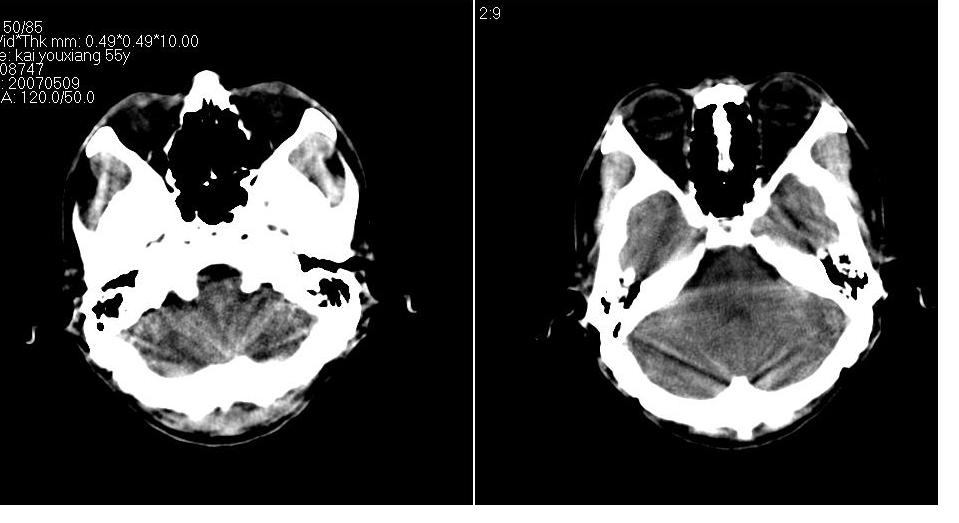

以下是引用tianhep在2007-5-9 19:53:00的发言:[br]这个部位多为苍白球钙化,苍白球钙化往往双侧对称。有外伤史而无症状。首先考虑为苍白球钙化。短期内复查一次就可。

以下是引用狙击手在2007-5-9 19:52:00的发言:[br]病灶边界模糊,外周无水肿带,无占位效应,无任何不适,考虑钙化。

以下是引用gyh6308在2007-5-9 21:10:00的发言:[br]这种病例我见过,是脑血管畸形所致的钙化,做cta可观察